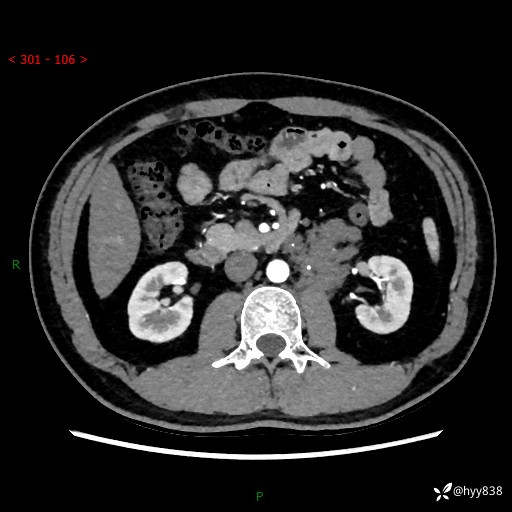

现病史:患者3月余前检查发现左侧腹膜后占位,大小约3.7*4.9cm,平素无腰疼,无肉眼血尿,无尿频尿急等不适,当时未特殊处理,在门诊复查CT提示左侧腹膜后占位,门诊拟“左侧腹膜后占位”收入院。 起病以来,患者精神佳,饮食、睡眠良好,大小便正常,体力体重无明显变化。

腹膜后CT平扫+增强